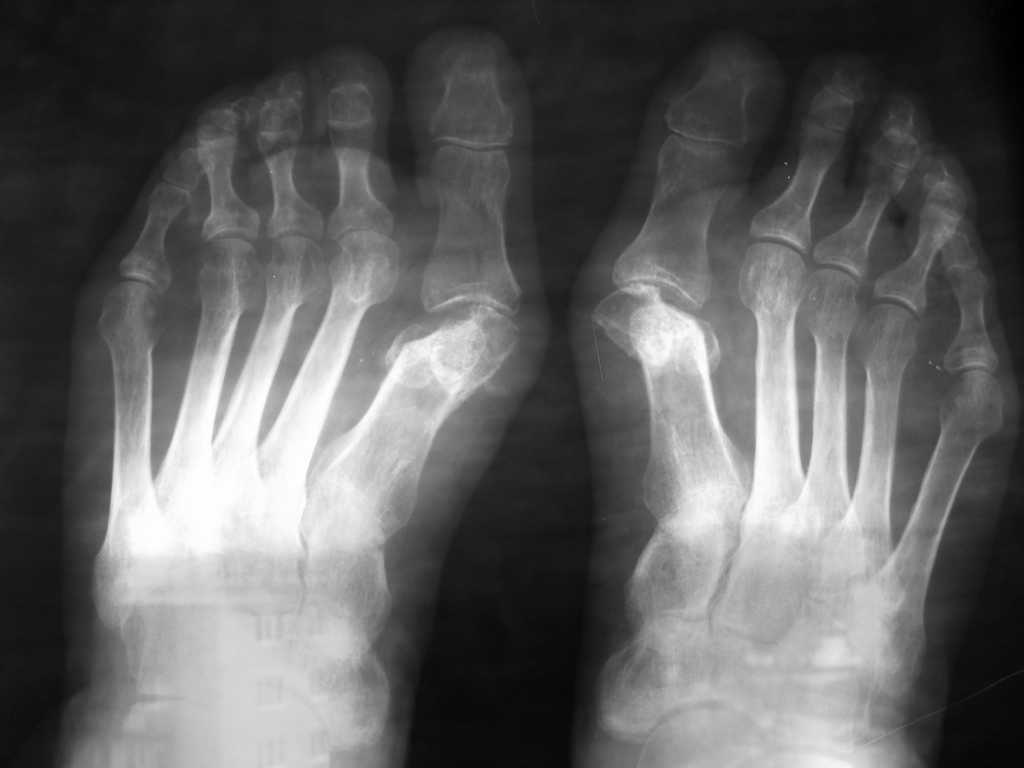

У пациентки после операции по поводу вальгусной деформации 1-х пальцев стоп, выполненной в одной из клиник нашего города 8 месяцев назад имеется картина асептического некроза головок 1-х плюсневых костей. Беспокоят боли в плюсне-фаланговых суставах, больше на правой ноге. (По-видимому, была выполнена операция Шаде-Бома с клиновидной резекцией головок 1-х плюсневых костей). Помогите советом. Мы думаем выполнить моделирующую резекцию головок плюсневых костей, удалить экзостозы, сформировать по возможности сферическую форму головок. Либо напрвить больную на эндопртезирование плюсне-фаланговых суставов.